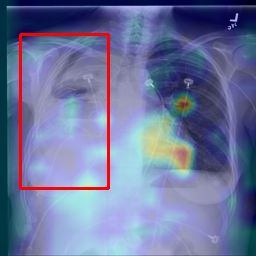

Deployments of artificial intelligence in medical diagnostics mandate not just accuracy and efficacy but also trust, emphasizing the need for explainability in machine decisions. The recent trend in automated medical image diagnostics leans towards the deployment of Transformer-based architectures, credited to their impressive capabilities. Since the self-attention feature of transformers contributes towards identifying crucial regions during the classification process, they enhance the trustability of the methods. However, the complex intricacies of these attention mechanisms may fall short of effectively pinpointing the regions of interest directly influencing AI decisions. Our research endeavors to innovate a unique attention block that underscores the correlation between 'regions' rather than 'pixels'. To address this challenge, we introduce an innovative system grounded in prototype learning, featuring an advanced self-attention mechanism that goes beyond conventional ad-hoc visual explanation techniques by offering comprehensible visual insights. A combined quantitative and qualitative methodological approach was used to demonstrate the effectiveness of the proposed method on the large-scale NIH chest X-ray dataset. Experimental results showed that our proposed method offers a promising direction for explainability, which can lead to the development of more trustable systems, which can facilitate easier and rapid adoption of such technology into routine clinics. The code is available at www.github.com/NUBagcilab/r2r_proto.